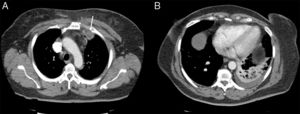

Mujer de 60 años, no fumadora, sin antecedentes de inmunosupresión ni factores de riesgo neumológicos. Acudió a urgencias por dolor pleurítico y en hombro izquierdo, fiebre de 38°C, tos sin expectoración e intenso dolor en la región medioclavicular y el hombro izquierdo. La radiografía de tórax mostró tenue infiltrado en el lóbulo inferior izquierdo (LII). A la exploración destacaba semiología de condensación y egofonía en campo inferior izquierdo. Presentaba una zona abultada muy dolorosa no fluctuante, sin signos inflamatorios en piel, en la región esternoclavicular izquierda alta. Se realizó fibrobroncoscopia, que mostró signos inflamatorios, y se remitieron muestras para anatomía patológica y microbiología. Los hemocultivos fueron negativos. El ecocardiograma no mostró lesiones valvulares ni vegetaciones sugestivas de endocarditis. Se inició tratamiento empírico con ceftriaxona y levofloxacino, con escasa respuesta clínica, precisando la administración de mórficos para control del dolor. La tomografía axial computarizada (TAC) torácica mostró cambios inflamatorios en el músculo pectoral izquierdo e imagen pseudonodular de 3,3×2,3cm, que se introducía entre la porción anterior del primer y segundo arco costal izquierdo, además de condensación pulmonar en LII con derrame pleural acompañante (fig. 1). Tanto la ecografía de cuello como la gammagrafía ósea confirmaron los hallazgos. Se realizó punción-aspiración con aguja fina (PAAF) guiada por ecografía, de la que se aisló S.aureus resistente a ampicilina y sensible a eritromicina, gentamicina, clindamicina, ciprofloxacino, levofloxacino y cotrimoxazol. En las muestras de la fibrobroncoscopia se aisló el mismo microorganismo. Durante el ingreso recibió tratamiento antibiótico intravenoso, según antibiograma, con ciprofloxacino y amoxicilina-clavulánico con mejoría clínica, radiológica y de los reactantes de fase aguda, sin precisar drenaje. Fue tratada de forma ambulatoria durante 40días con resolución completa del cuadro.